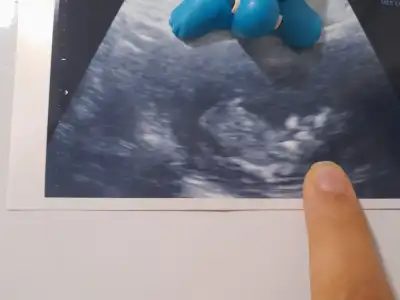

Sağol canım. Valla göründü doktorda dedi görüyomusun güldüğünü dedi öyle farkettim. Görseli de var atsa mıHayırlı olsun. Gülüşü görünüyormu ya 3 ayda :)

Ayyyy maşallah yaBebişimin gülüşü farkeden var mı. Çektiğimiz videodan çektim görseli